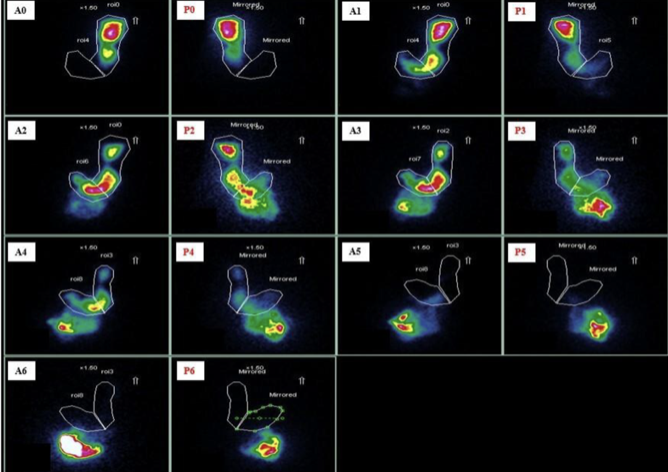

Scintigraphy

Which imaging to assess for gastric emptying for gastroparesis?

radioactive scrambled eggs ☢